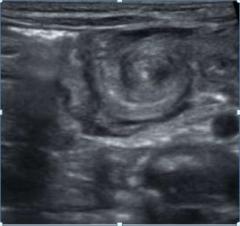

Se realizó una radiografía de abdomen, observándose distensión gástrica con adecuada distribución aérea intestinal. Luego se le realiza una ecografía abdominal con Doppler color, obteniéndose los siguientes hallazgos:

Figura 1. Corte transversal a nivel epigástrico.

Figura 2. Corte transversal a nivel epigástrico con Doppler color.

Teniendo en cuenta la clínica del paciente y los hallazgos imagenológicos, ¿Qué diagnóstico considera en primera instancia?

a. Invaginación intestinal

b. Malrotación intestinal con vólvulo

c. Atresia ileal.